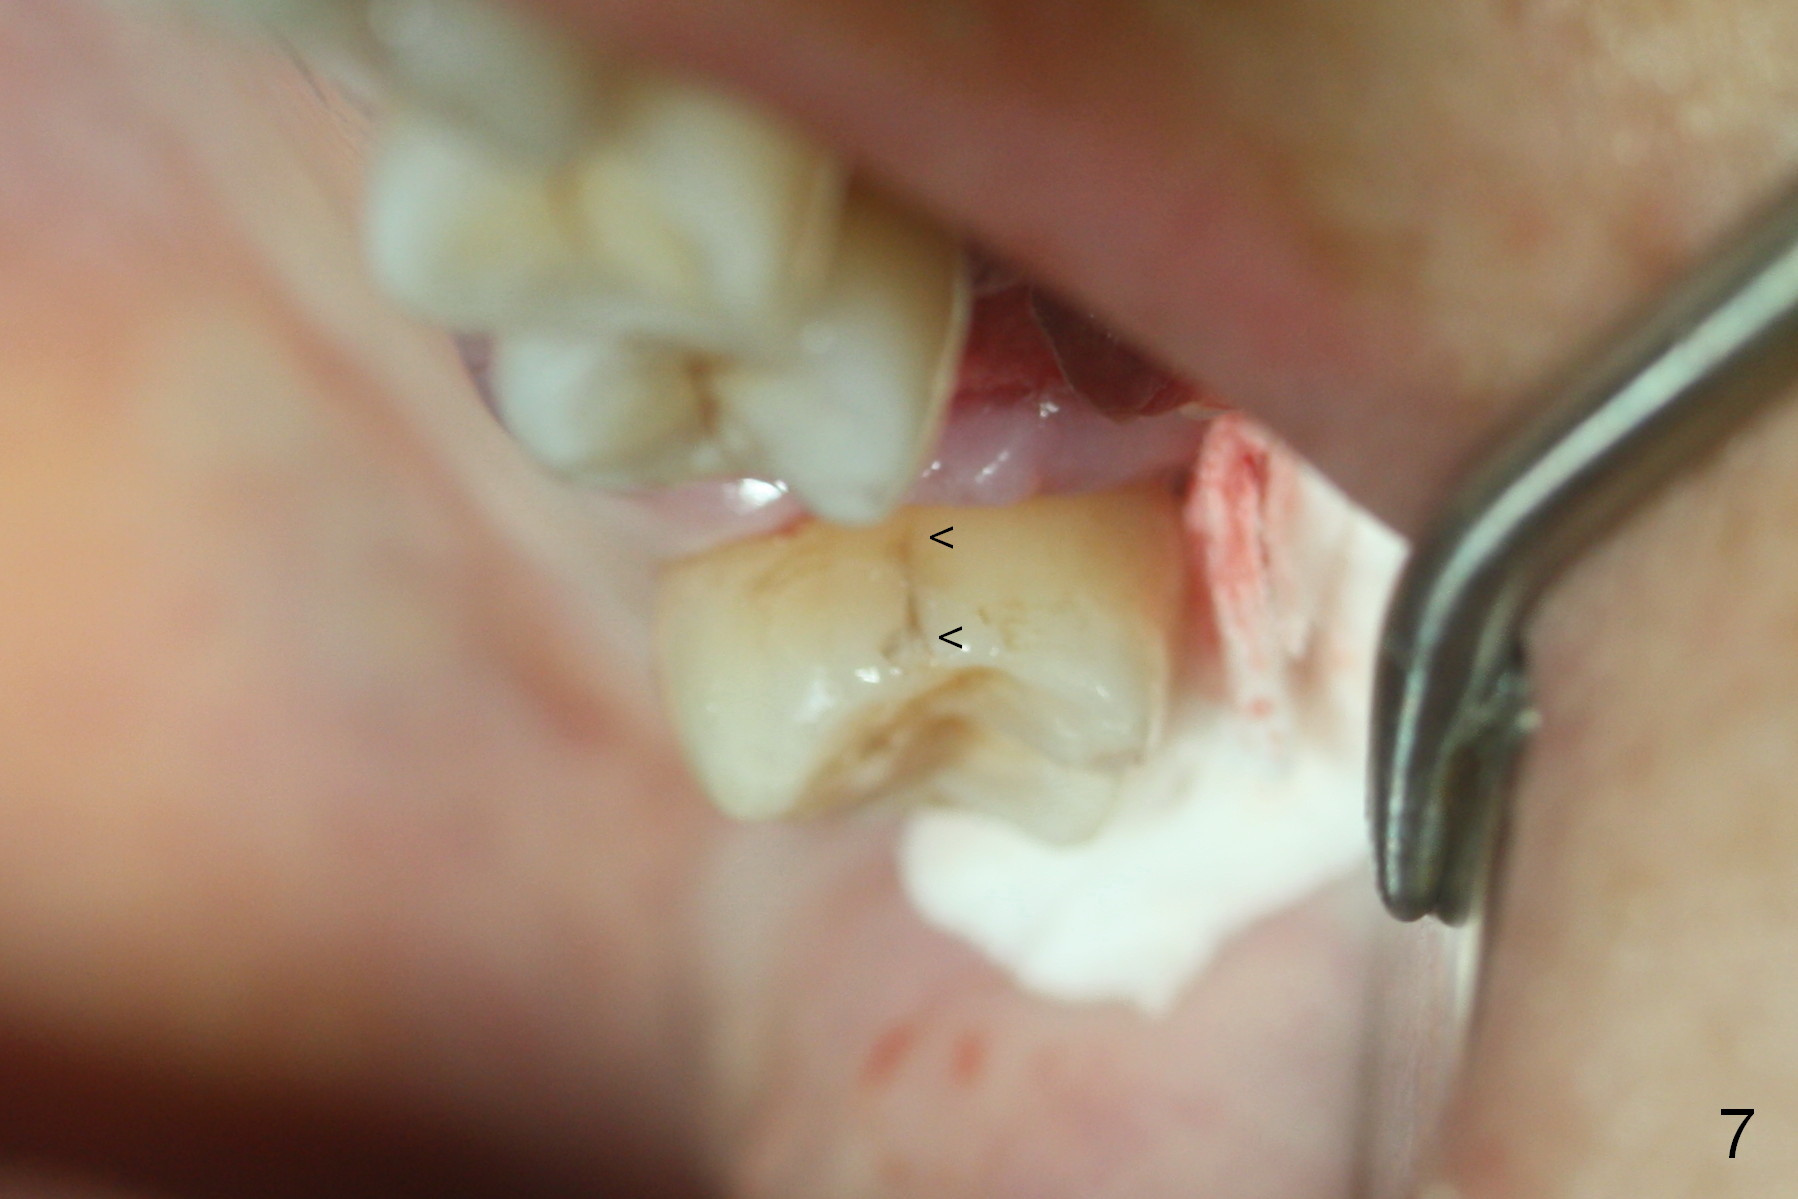

When the tooth is extracted, the lingual crack line (Fig.4 white <) is contiguous with the mesiobuccal one (black >). The latter corresponds to the white arrowheads in Fig.2. In all the crack line is extensive. The buccal and palatal plates are defective coronally. The large granulation tissue in the furca (Fig.5 *) suggests bone loss in the crestal septum. Most surprising is a crack line in the distal surface of the tooth #13 (Fig.6 ^) and in the mesial surface of #15 (Fig.7). Night guard will be fabricated after an implant crown is cemented at #14.